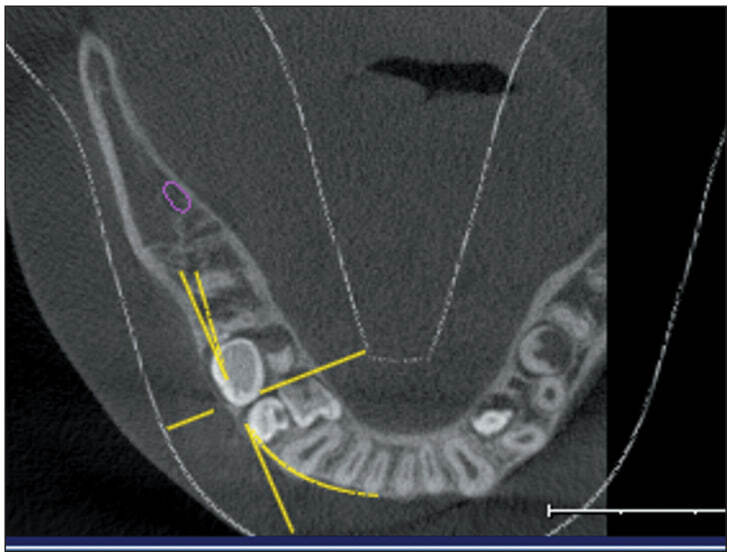

Изучено положение сверхкомплектных зубов, локализующихся в области верхушки альвеолярного гребня с язычной стороны 4.4 и 4.5 зубов. Оказалось, что мезиальный сверхкомплектный зуб расположен горизонтально в направлении зубной дуги, а бугры дистального направлены в язычную сторону. Признаки патологии костной ткани не обнаружены (рис. 4).

Рис. 4. Компьютерная томография нижней челюсти пациента Ф. А., 12 лет

Дальнейшее ортодонтическое воздействие при помощи нижнечелюстной пластинки с расширяющим и удлиняющим зубной ряд винтами и искусственными зубами в боковых отделах было направлено на создание места в зубной дуге для прорезывания ретенированных премоляров нижней челюсти. Произведено удаление сверхкомплектных зубов в области 4.4 и 4.5 зубов. Через восемь месяцев отмечено прорезывание премоляров нижней челюсти справа (рис. 5).